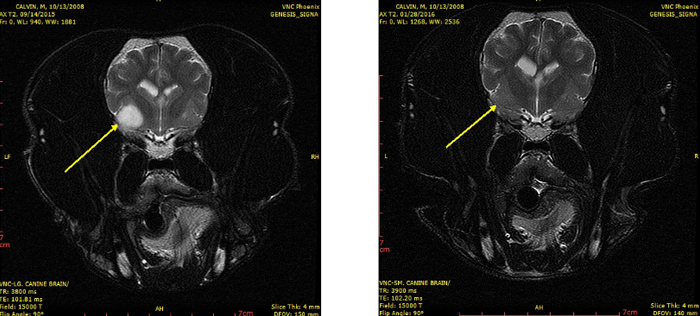

MRI confirmed the suspicion—it revealed a fairly large mass on Calvin’s brain. Calvin was a good candidate for stereotactic radiosurgery—the treatment could eliminate his tumor.

Calvin’s parents agreed to the procedure. Calvin received treatment over three days. He had a seizure on the first day, but otherwise, everything went smoothly. Calvin had no further seizures, and a follow-up MRI was clear.